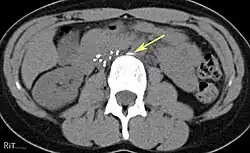

For patients who have been denied MRI scans for safety reasons, doctors usually recommend the CT scan with contrast as an alternative.

Placement

IVC filters are placed endovascularly, meaning that they are inserted via the blood vessels. Historically, IVC filters were placed surgically, but with modern filters that can be compressed into much thinner catheters, access to the venous system can be obtained via the femoral vein (the large vein in the groin), the internal jugular vein (the large vein in the neck) or the arm veins with one design. Choice of route depends mainly on the number and location of any blood clot within the venous system. To place the filter, a catheter is guided into the IVC using fluoroscopic guidance, then the filter is pushed through the catheter and deployed into the desired location, usually just below the junction of the IVC and the lowest renal vein.[44]

Review of prior cross-sectional imaging or a venogram of the IVC is performed before deploying the filter to assess for potential anatomic variations, thrombi within the IVC, or areas of stenoses, as well as to estimate the diameter of the IVC. Rarely, ultrasound-guided placement is preferred in the setting of contrast allergy, chronic kidney disease, and when patient immobility is desired. The size of the IVC may affect which filter is deployed, as some (such as the Birds Nest) are approved to accommodate larger cavae. There are situations where the filter is placed above the renal veins (e.g. pregnant patients or women of childbearing age, renal or gonadal vein thromboses, etc.). Also, if there is duplication of the IVC, the filter is placed above the confluence of the two IVCs [45] or a filter can be placed within each IVC.[46]